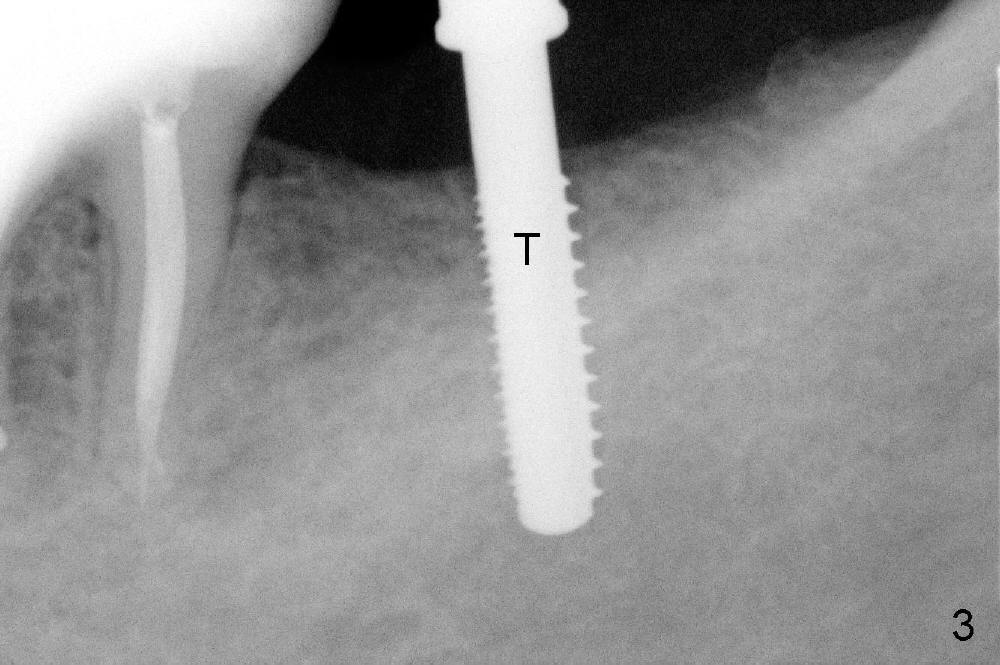

Planning gives the surgery and assistants confidence. Implant placement seems to be more smoothly. A preop PA (Fig.1) shows that the periapical radiolucency of the neighboring tooth #19 disappears. Removal of the residual roots of the teeth #17 and 18 (Fig.1 *) gives rise to a nice surgical field (Fig.2, the sockets packed with Clindamycin soaked gauze). Immediate implant osteotomy is formed as mesial as possible of the wound. Attention is being paid to buccolingual trajectory when the first pilot drill is used (not shown). An intraop PA is taken with a 3.8 mm tap in place to confirm the depth of the osteotomy relative to the inferior alveolar canal (Fig.3). A 4.5x12 mm implant is placed as planned (Fig.4). The elongated wound (mesiodistally) allows the wound to approximate around the implant/healing abutment with sutures (Fig.5). The gingiva heals 8 days postop (Fig.6). The 1st 4 coronal threads remains outside the bone 3.5 months postop (Fig.7 >). It appears that less thread exposure 1 year 7 months postop (Fig.8), suggesting bone growth. To prevent periimplantitis and facilitate restoration, place 2nd molar implant as deep as possible with slightly shorter implant.